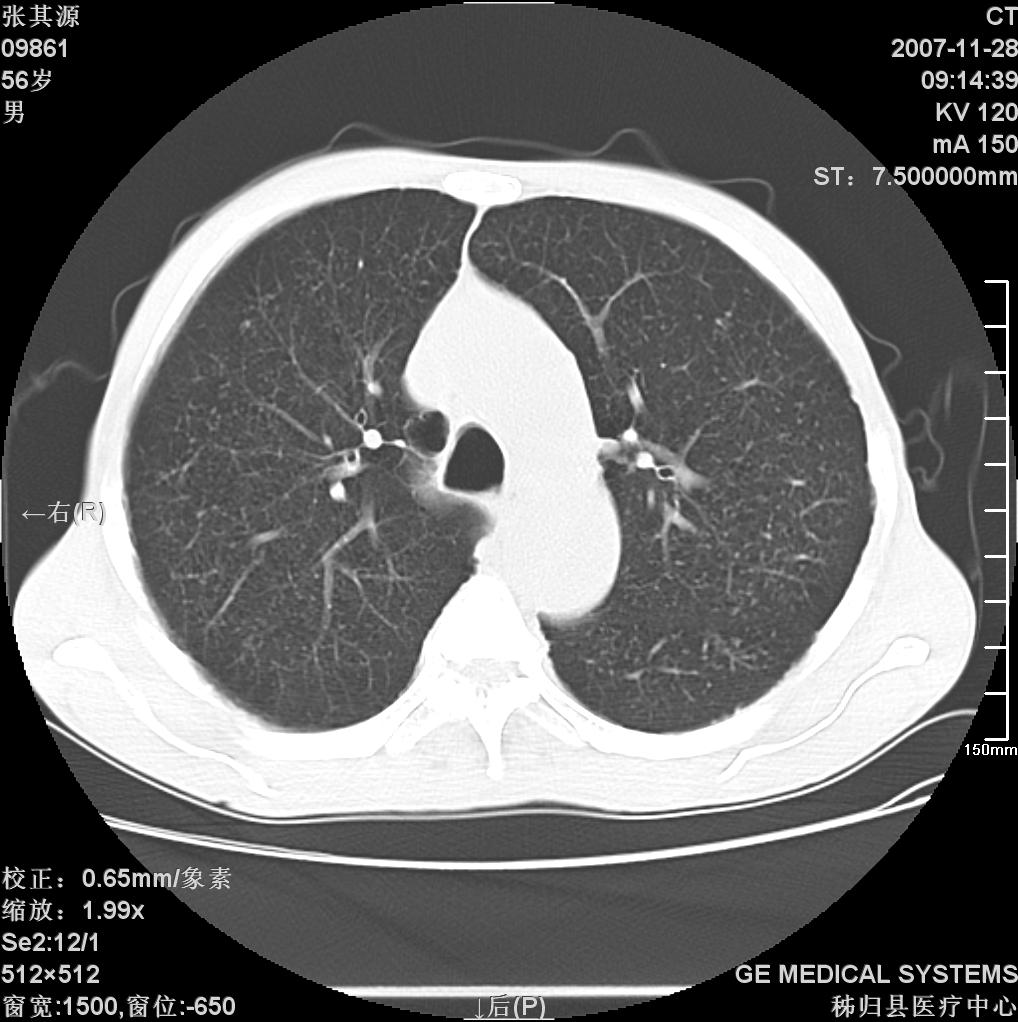

患者因阻塞性黄疸入院,发病前10天持续中等程度发烧.术前检查发现两肺弥漫性病变,请各位大虾会诊,除了考虑急性血源性肺结核外,还有其他什么疾病可能.

两肺另见略大结节,结合病史,应考虑转移,有腹部片吗?肺内表现可有:结核?甲状腺癌肺转移?肺泡癌?

双肺多发粟粒样病灶,右肺胸膜下结节样病灶,气管前腔静脉后及隆突下均见肿大淋巴结,结合胆道肿瘤病史首先考虑转移。另外心影密度略低,时间格显示,是否有贫血?查明白再手术吧!